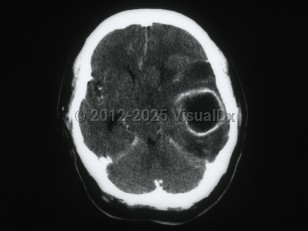

Brain abscess is a focal intracerebral infection that begins with inflammation and progresses to a localized collection of pus. Bacteria, followed by fungi and parasites, most commonly cause it. Infection may be introduced hematogenously (bacteremia, fungemia), from contiguous areas (dental, sinus and ear infections, meningitis), via trauma, or by iatrogenic route (invasive neurosurgical procedures). In about 15% of cases, no source is identifiable.

Infection can be introduced via blood, from contiguous sites, or through trauma or surgery. Early cerebritis sets in following an inflammatory cell response (days 1-3), necrosis (days 4-9), and development of a collagen capsule (days 10-14).